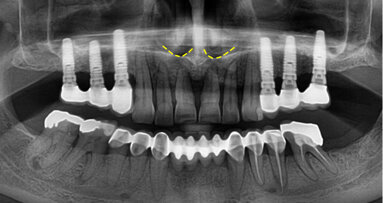

Dvaadvacetiletý pacient byl na naši kliniku odeslán z důvodu bolestivosti zubů 45 a 46. Jednalo se o celkově zdravého pacienta s mírnou až akutní bolestivostí zubů na poklep. Odesílající lékař byl znepokojen celkovou anatomií. Po zhotovení preoperativního rentgenového snímku (Obr. 4) byl proveden trepanační otvor pomocí vrtáčku Crown Cutter a vrtáčku s neaktivní pracovní částí (KOMET/Gebr. Brasseler). Úprava obrysu kavity byla provedena Start-X-ultrazvukovou koncovkou č. 1 a Muellerovým vrtáčkem č. 3 (Mani, Inc.; obr. 5).

Vstupy do kořenových kanálků byly zkalcifikované, přístup byl získán pomocí nástroje ProTaper SX, který byl veden kartáčovitým pohybem. Opracování kanálků bylo provedeno 10.02 K-Flexofilem (DENTSPLY Maillefer) za pomocí Glyde Gel (DENTSPLY Maillefer). Průchodnost byla ověřena PathFily a kanálky byly opracovány za použití ProTaper Systému (DENTSPLY Maillerfer). Po apikálním tvarování byly čtyři kanálky opracovány nástrojem ProTaper F3 s irigací 5% roztokem hypochlornanu sodného. Finální výplach byl proveden ultrazvukově aktivovaným 5% roztokem hypochloridu sodného, 40% roztokem kyseliny citronové a 95% etanolem. Kořenová výplň byla zhotovena pomocí Alpha II a Beta zařízení za použití techniky kontinuální kondenzační vlny a vstup do kořenových kanálků byl uzavřen kompozitem (Gradia Flow; Obr. 6).

Zub byl postendodonticky zrekonstruován pomocí čepu vyztuženého skelnými vlákny a kompozita (Core-X Flow a Ceram-X Duo, DENTSPLY DeTrey) a byl zhotoven pooperační RTG snímek (Obr. 7).